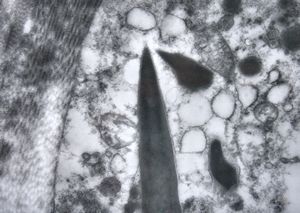

F,76y. | intranuclear needle-like structures - rhabdomyoma,tongue

F,76y. | intranuclear needle-like structures - rhabdomyoma,tongue